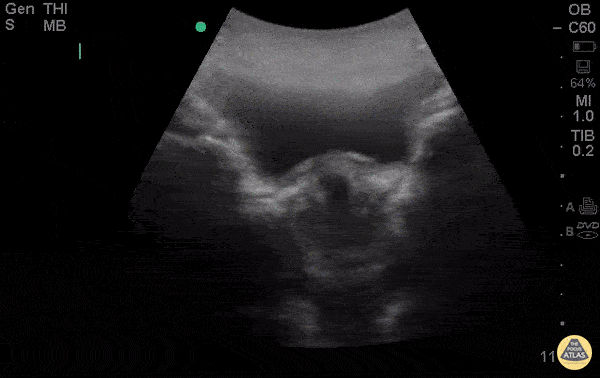

28yo F G5P4 presenting at 8 weeks pregnant by LMP for pelvic pain and vaginal bleeding for 2 days. POCUS demonstrates an anechoic gestational sac without a visible yolk sac of fetal pole, progressing past the cervix. The patient had a spontaneous abortion in the ER, passing products of conception shortly after the POCUS. Esther Kwak, MD, Ian Desouza, MD- Kings County/SUNY Downstate Emergency Medicine